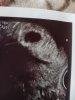

Hej dziewczyny. U mnie beta wczoraj 867 i usg wskazują jakoś ma 4/5 tydzien dopiero, więc termin raczej na maj. Życzę Wam miłych i nudnych juz teraz 8 miesiecy❤❤❤

No mi jakby podobnie. Jest pęcherzyk, ciałko żółte, początek ciąży.@Majjka. To mamy identycznie 5t5d - wstawiłam zdjęcie z moje dzisiejszego usg- też malutki pęcherzyk i ciało żółte, ale naprawdę słabo widoczne i według mojego lekarza wszystko jest ok. A Twój co powiedział?